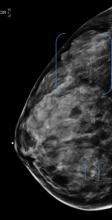

AI is also helping simplify complex tasks and help reduce the reading time on involved exams. One example of this is in 3-D breast tomosythesis with hundreds of images, which is rapidly replacing 2-D mammography, which only produces 4 images. Another example is automated image reconstruction algorithms to significantly reduce manual work. AI also is now being integrated directly into several vendors' imaging systems to speed workflow and improve image quality.